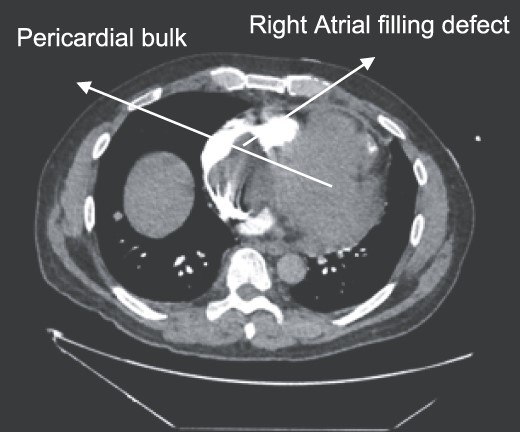

A 52-year-old gentleman was admitted to a district general hospital for shortness of breath causing type 1 respiratory failure with oxygen saturations of <90% despite high flow oxygen. His past medical history was unremarkable, and he was usually fit and well. A CT Pulmonary Angiogram (CTPA) was undertaken, which showed a heterogeneous oval-shaped lesion measuring 15 × 9 × 14 cm3 between the heart and the diaphragm, with a median attenuation of 35 HU and no enhancement during the arterial phase. Further solid lesions of 14 mm in the right lower lobe and 5 mm in the right upper lobe raised the suspicion of a primary cardiac sarcoma with pulmonary metastasis. This is shown in Fig. 1. Subsequent urgent CT staging (Fig. 2) was undertaken, which confirmed an indeterminate space occupying the inferior pericardial space, right atrial (RA) filling defect and anterior nodular pericardial thickening. No intra-abdominal or bone lesions were identified. An echocardiogram also confirmed these finding with the addition of no flow through the tricuspid valve (TV), as shown in Fig. 3.

CT thorax-abdomen pelvis, depicting the RA filling defect as well as pericardial bulk.